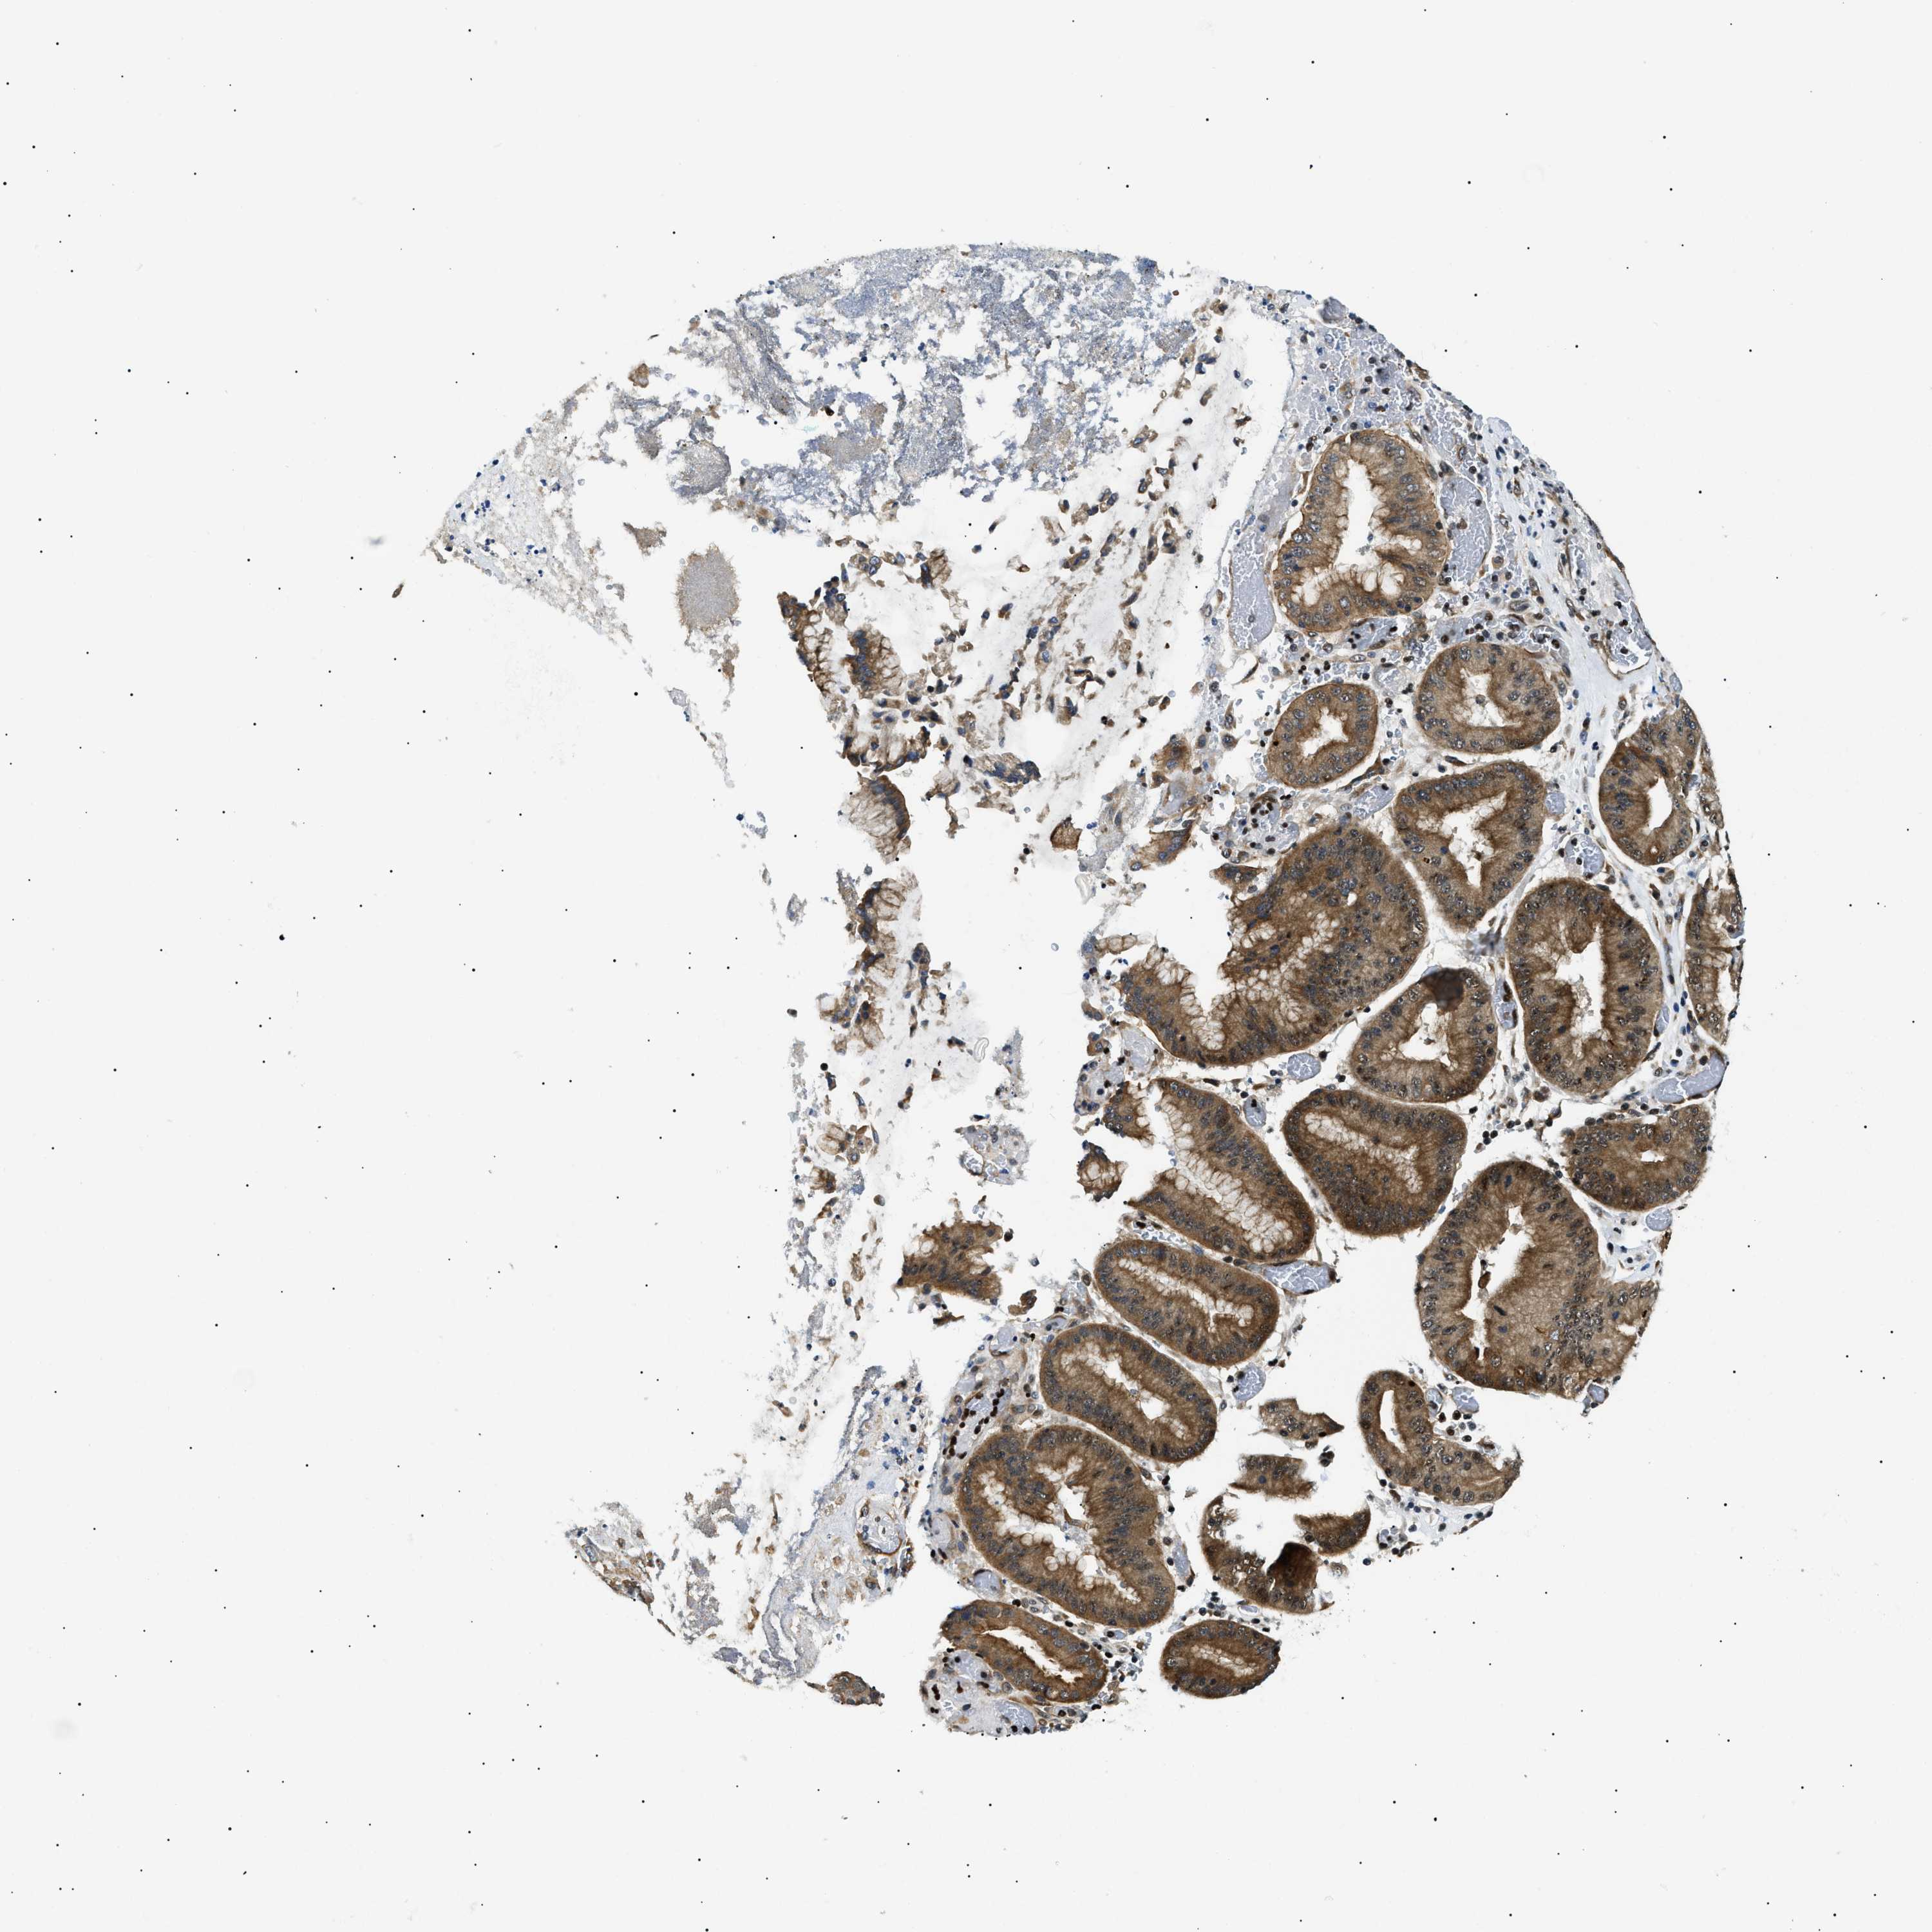

STOMACH CANCER - Protein expressioni

A mouse-over function shows sample information and annotation data. Click on an image to view it in a full screen mode. Samples can be filtered based on level of antibody staining by selecting one or several of the following categories: high, medium, low and not detected. The assay and annotation is described here.

Note that samples used for immunohistochemistry by the Human Protein Atlas do not correspond to samples in the TCGA dataset.

Antibody stainingi

Antibody staining in the annotated cell types in the current human tissue is reported as not detected, low, medium, or high, based on conventional immunohistochemistry profiling in selected tissues. This score is based on the combination of the staining intensity and fraction of stained cells.

Each image is clickable and will lead to virtual microscopy that enables deeper exploration of all samples and also displays staining intensity scores, fraction scores and subcellular localization as well as patient and tissue information for each sample.

Antibody HPA062997

Antibody CAB014874

Staining

High

Medium

Low

Not detected

Intensity

Strong

Moderate

Weak

Negative

Quantity

>75%

75%-25%

<25%

None

Location

Nuclear

Cytoplasmic/membranous

Cytoplasmic/membranous,nuclear

Adenocarcinoma, NOS